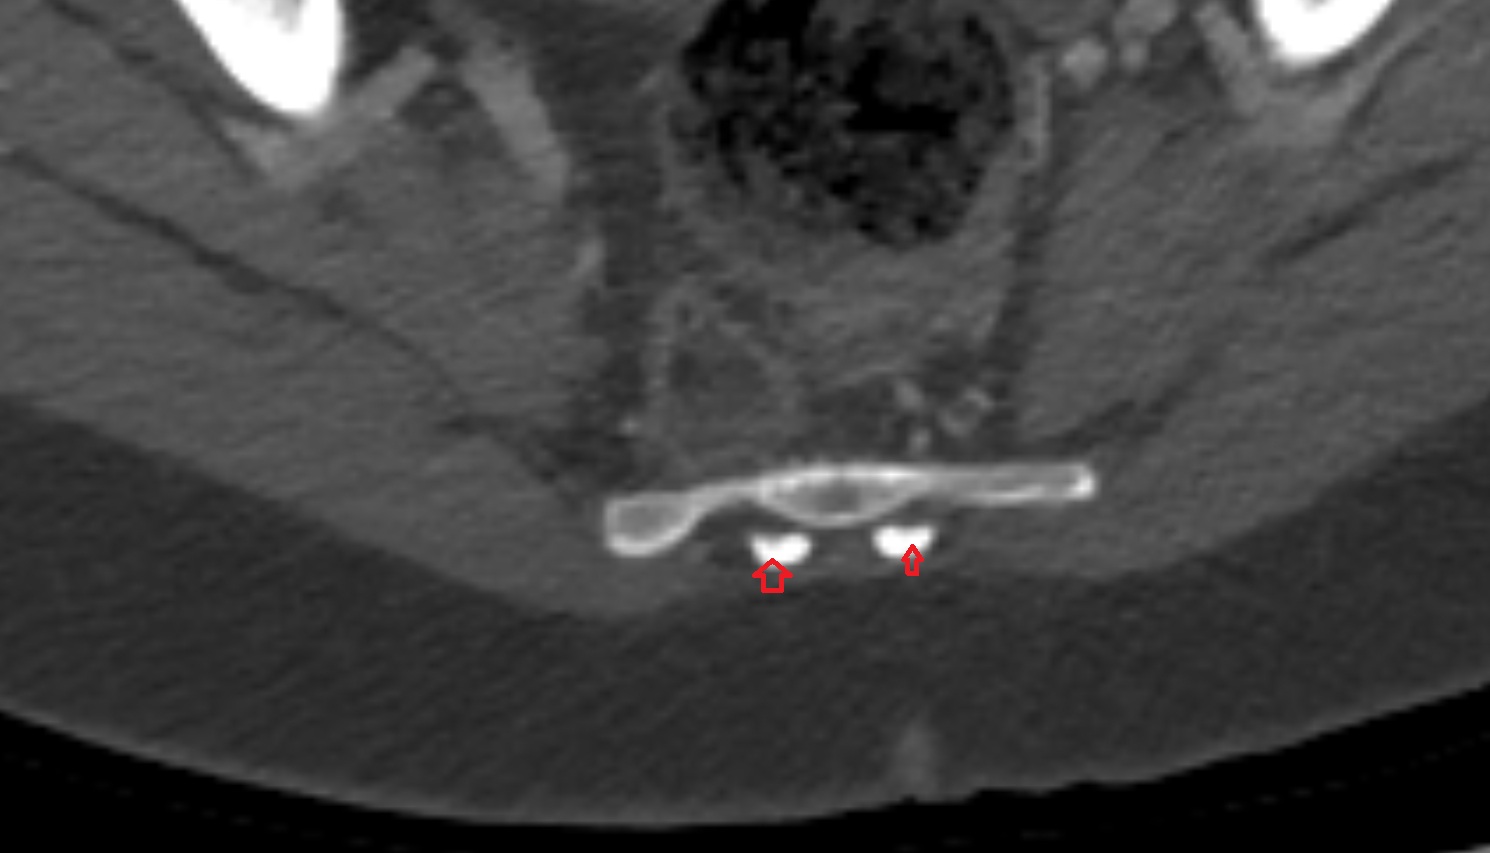

- Pubic symphysis